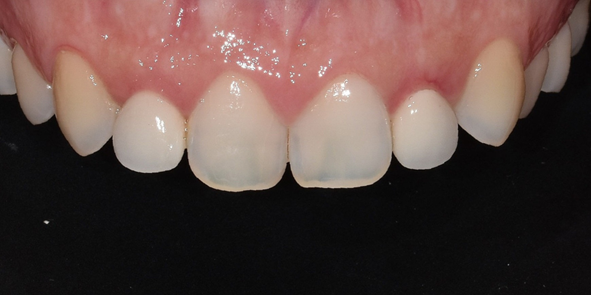

(좌) 2022-04-01, (우) 2022-05-26

다양한 왜소치 사례

대문니의 약 70~80% 정도의 비율이 측절치의 정상적인 크기라고 한다면, 이보다 훨씬 더 작은 왜소치로 형성되는 것이죠.